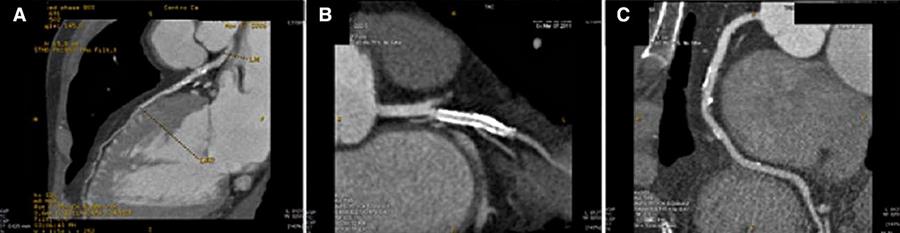

Paziente di 59 anni con precedente IMA e PCI con stent alla intermedia. L’insorgenza di dolore toracico ha indicato l’esecuzione di un’angio-TC come test di prima linea. Questa ha evidenziato una stenosi del 55% del tratto prossimale del ramo discendente anteriore (A), pervietà dello stent (B), e una stenosi del 65% a livello del tratto medio della coronaria destra (C).